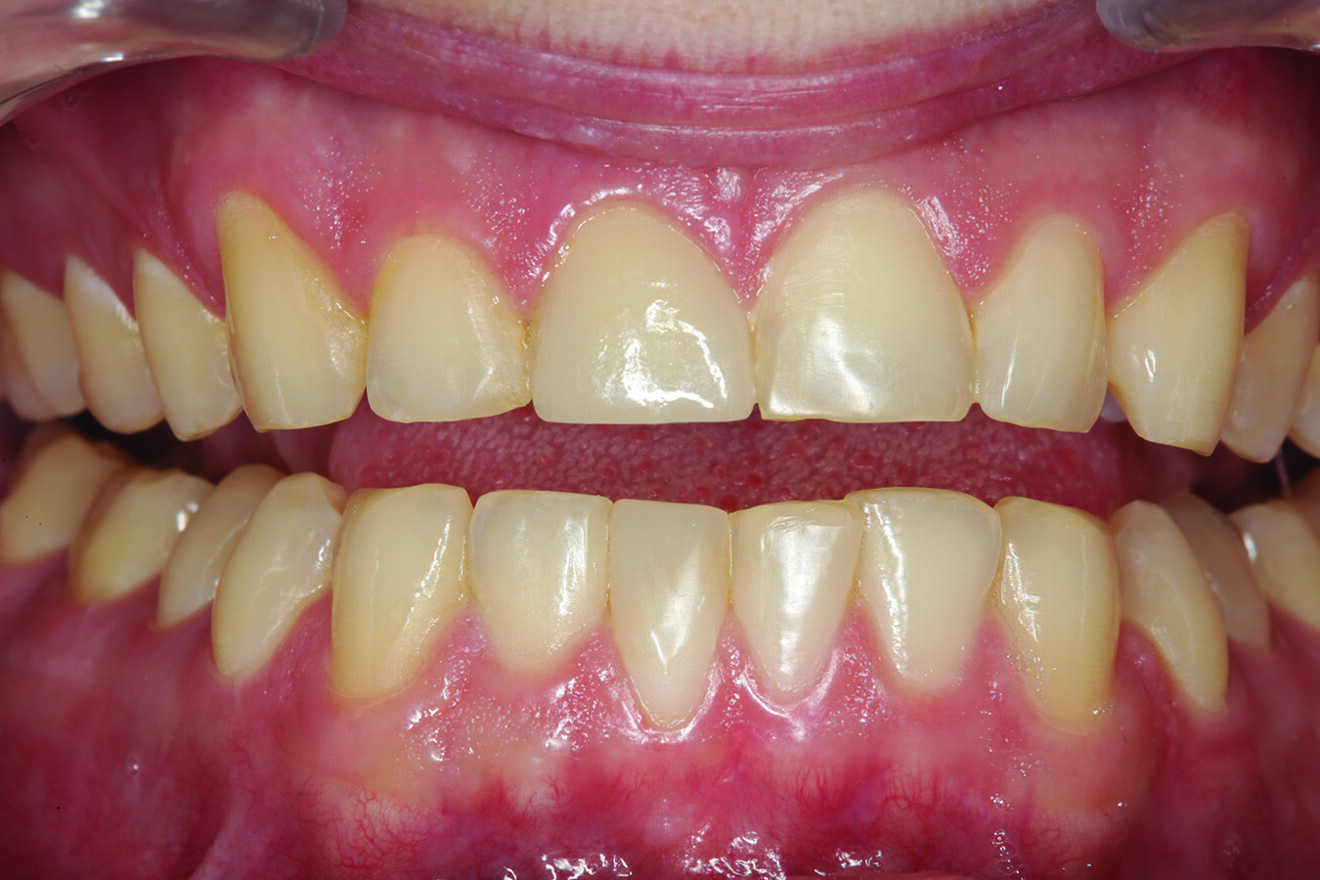

Fig. 3: Incisal view showing that tooth #41 was the arch form’s most facially positioned mandibular incisor.

What about the alignment of the opposing teeth? It could be observed that excessive wear was present on the incisal edges of teeth #31 and 41 (Fig. 2). From the incisal view, exten­sive wear was seen on all mandibular inci­sal edges due to occlusal disease—which is often seen yet left untreated (Fig. 3). Tooth #41 was also facially positioned so that in pro­trusive excursion it engaged the palatal surface of tooth #11 prematurely, placing addi­tional stress on both the palatal surface and inci­sal edge of tooth #11 before coupling with the remainder of the maxillary anterior segment. This demonstrates that addressing these issues restoratively involves more than just fixing a chipped composite restoration.